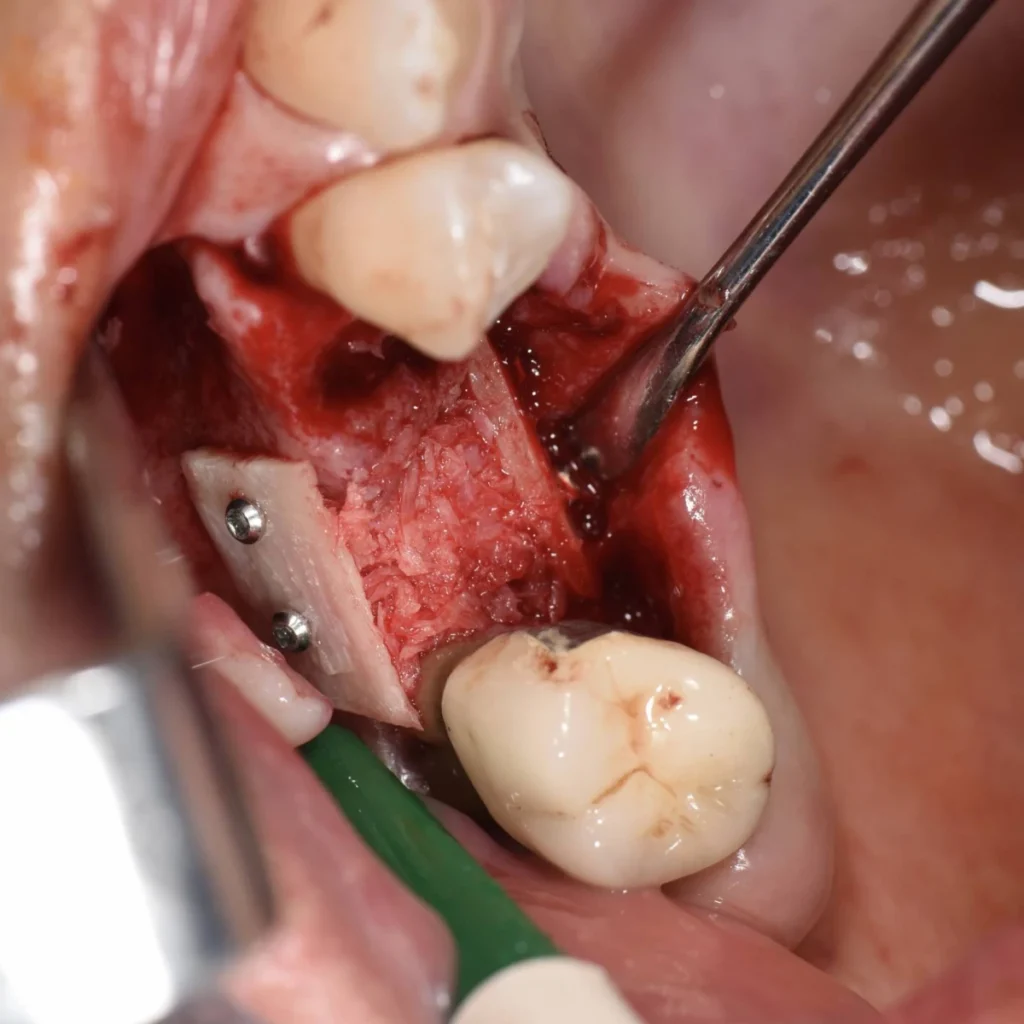

- Après discussion avec la patiente, il est décidé d’effectuer une greffe autogène, véritable « gold standard » dans ce genre de situation.

- L’intervention est réalisée sous anesthésie locale.

- Il s’agit de prélever un greffon osseux dans la zone postérieure de la machoire inférieure de la patiente. Ce greffon est ensuite modelé et transfixé avec des vis au niveau du site à traiter.

- La gencive est ensuite refermée avec des sutures.